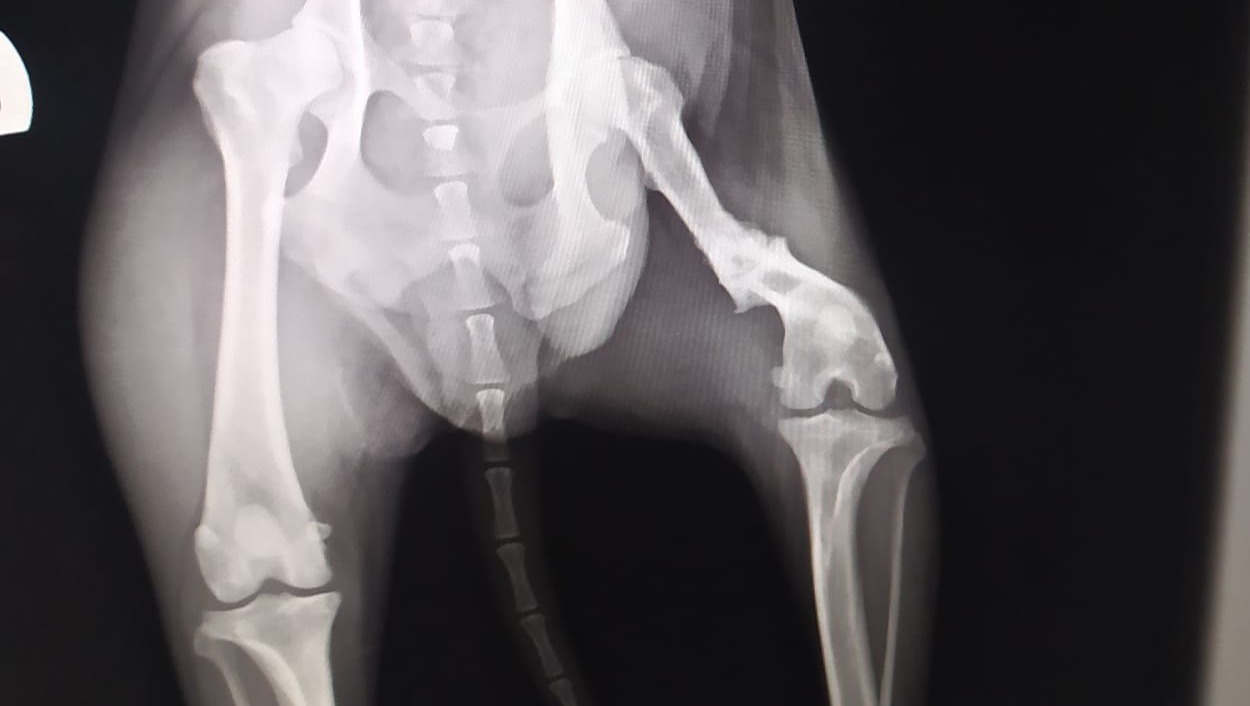

Se le colocó un clavo intramedular, una placa y 10 tornillos. También le realizaron un injerto de hueso que sacaron de su pelvis.

Tuvimos revisón el día 21. Va todo estupendamente, la aguja intramedular, la placa y los tornillos siguen en su sitio. El ingerto de hueso se va desarrollando perfectamente y esta osifocando muy bien. Aun le queda recuperacion hasta que el hueso suelde por completo.

Estas son las radiografías que se le hicieron tras la operación.

Y estas las que se le hicieron el dia de la revisión.